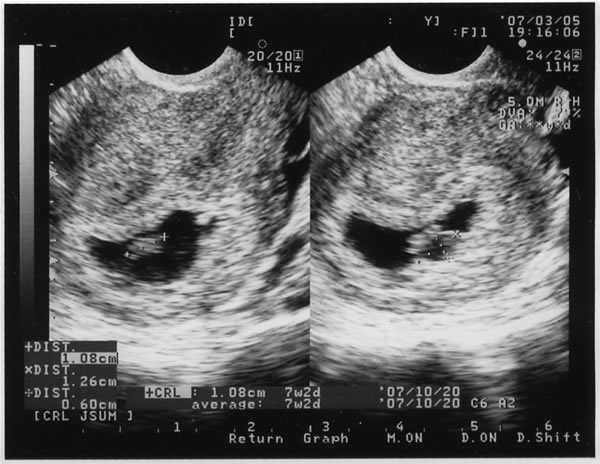

3月上旬、嫁がエコー写真なる物を持って来る。

何だか塊状の物が写っているだけ・・・。

心臓も、頭も出来上がっていない状態なのだとか。 ふむふむ。

数字を見ると、1.8cm・・・ちっさーぁぁぁぁい

指の先くらいの大きさやね。

でも、目に見える我が子との初対面に、じーぃぃぃぃん となる。